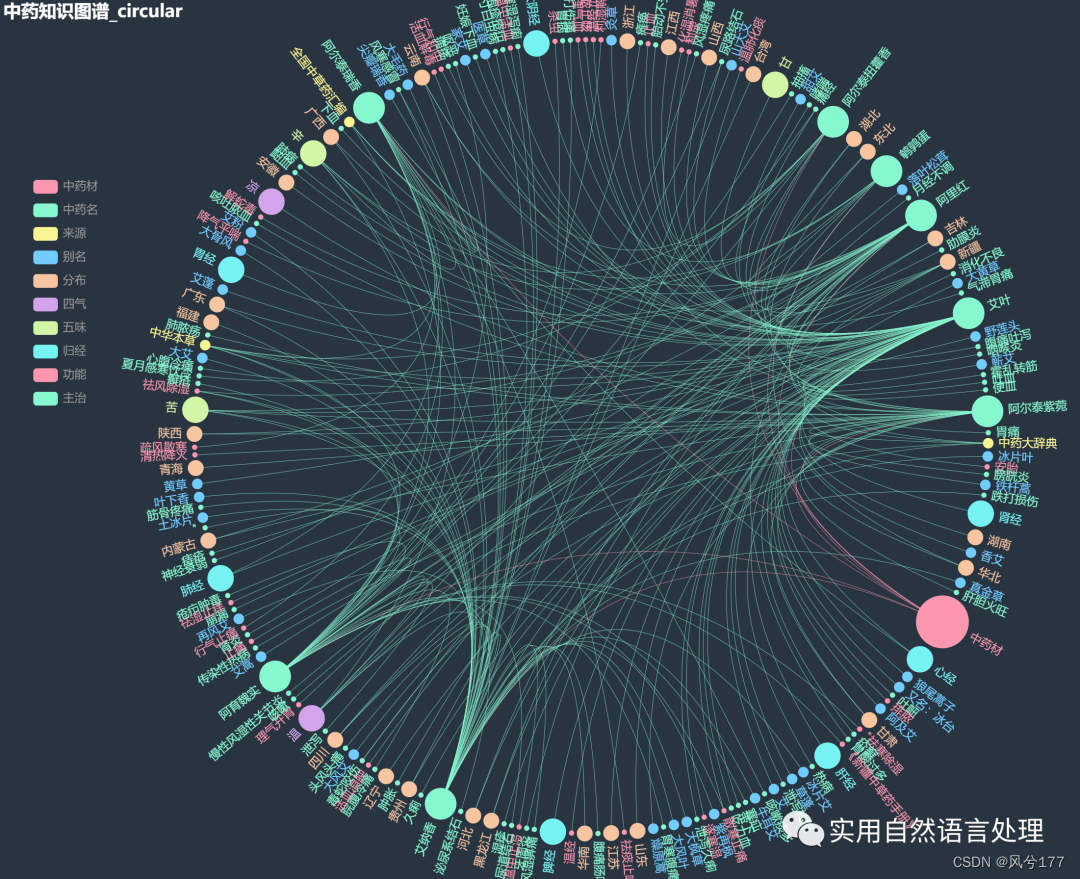

少量数据的中药知识图谱-环形图

少量数据的中药知识图谱-环形图(部分节点展示图1)

本文将基于pyecharts框架,对中药材知识图谱进行“力导图”和“环形分布”可视化,同时,对中药材地理分布、来源和别名关系进行分析与可视化。

2.2 中药材知识图谱可视化

前文自顶向下构建中药知识图谱初探已经介绍了中药材知识图谱的构建和neo4j可视化过程,接下来将对该图谱数据利用pyecharts进行可视化。